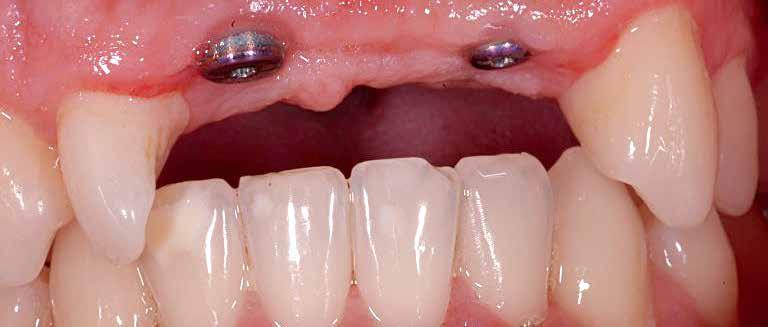

A systemic antibiotic (2g amoxicillin-clavulanic acid, per-orally) was administered to the patients 1 hour prior to the procedure. The patient’s mouth was rinsed with a solution of chlorhexidinedigluconate 0.2% for 2 minutes. After surgical guide printing, the tooth was extracted and the implant placed (IDI implant Implants Di usion International 23/25) following implant placement protocol using a fully guided CAD CAM surgical guide. 14 (fig 3,4,5)

Figure 5: Fully guided implant placement through the surgical guide using spoons. The implant was inserted at the planned position.